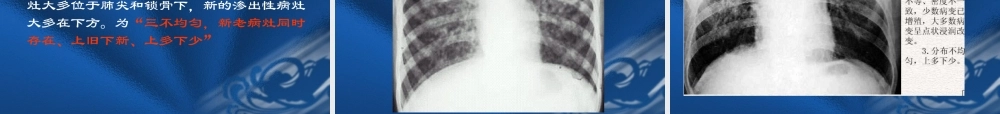

肺结核 肺结核是结核杆菌在肺内所引起的常见的慢性传染性疾病,肺结核的诊断主要以临床症状、痰检、胸部 X 线检查等。 【临床与病理】 肺结核的临床表现与感染的结核杆菌的数量、毒力及机体免疫反应和变态反应状态有关,也与病变的发展阶段有关。临床症状表现为咳嗽、咯血、胸痛、低热盗汗、乏力、食欲减退和明显消瘦等。痰检可找到结核菌。 肺部基本病变的性质可分为: 1 、渗出性病变; 2 、增殖性病变; 3 、变质性病变。 结核病分类:1 、原发型肺结核(Ⅰ型):原发综合征和胸内淋巴结结核。2 、血行播散型肺结核(Ⅱ型):急性粟粒型肺结核和亚急性或慢性血行播散型肺结核。3 、继发型肺结核(Ⅲ型):渗出浸润型、干酪型和空洞型肺结核。4 、结核性胸膜炎( Ⅳ型 ):结核性干性胸膜炎、结核性渗出性胸膜炎和结核性脓胸。5 、其它肺外结核(Ⅴ型):如骨结核、肾结核等。 一、原发性肺结核 机体初次感染结核菌所引起的肺结核称为原发性肺结核,原发性肺结核常见于儿童,少数可见于青年。(一)原发综合症:结核杆菌经呼吸道吸入后,经支气管、细支气管、肺泡管到肺泡、在肺实质内产生急性渗出性炎症性改变,其大小多数为 0.5~ 2CM ,这种局限性炎性实变称为原发病灶。同时原发病灶内的结核杆菌很快经淋巴管向局部淋巴结蔓延,引起结核性淋巴管炎与结核性淋巴结炎。肺部原发灶、局部淋巴管炎和所属淋巴结炎三者称为原发综合症。 【 X 线表现】 原发病灶表现为云絮状或类圆形密度增高影,也可以表现为肺段或肺叶范围的片状或大片状密度增高影,边缘模糊不清,可见于肺部任何位置,多见于上叶的下部或下叶后部靠近胸膜处。肺门或纵膈肿大淋巴结表现突出于 正常组织轮廓的肿块影,自发病灶引向肿大淋巴结的淋巴管炎,表现为一条或数条较模糊的条索状密度增高影。典型的原发综合征显示原发病灶、淋巴管炎与肿大的肺门淋巴结连接在一起,形成哑铃状。 (二)胸内淋巴结结核:原发综合症为原发性肺结核的典型表现,但原发病灶的病理反应一般较轻,易被吸收或掩盖,由于淋巴结内干酪样坏死较严重,其吸收愈合的速度较原发病灶缓慢,当原发病灶完全吸收时,纵膈和(或)肺门淋巴结肿大则成为原发性肺结核的重要表现,称为胸内淋巴结结核。淋巴结肿大常伴周围组织渗出性炎性浸润,称为炎症型。淋巴结周围炎吸收后,在淋巴结周围有一层结缔组织包绕,称为结节型。肿大淋巴结有压迫支气管引起肺不张,以右上叶或右中叶...